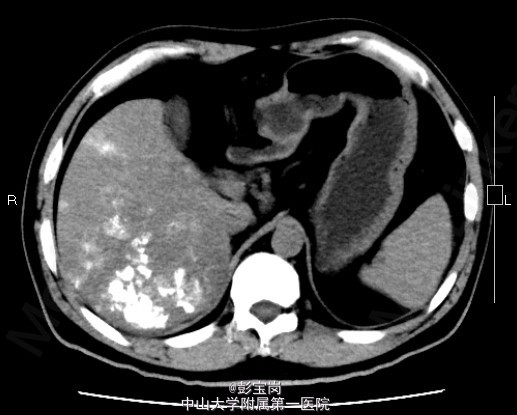

男性,42岁;因“肝癌行TACE术后,拟行手术治疗”入院。患者1月前体检发现原发性肝癌,于25天前在外院行肝动脉栓塞化疗(TACE)术。2天前患者就诊我院,查上腹CT示:右肝后叶多发结节或肿块,碘油栓塞后改变,病灶内和周边部仍有血供,门脉右后下支癌栓形成。现为进一步诊治门诊拟“肝细胞癌”收住我科。起病以来,精神食欲可,大小便通畅,体重无明显变化。既往史肾结石病史,否认肝炎病史。

查体无特殊; 检验:白细胞WBC:13.27;血红蛋白Hb:121g/L;血小板PLT:225x10^9/L;肿瘤标记物:甲胎蛋白(AFP)111.32 ug/L;癌胚抗原(CEA)9.40 ug/L;CA125 20.2 U/mL;CA19-9 11.04 U/L;HBsAg(+)

诊断:肝细胞癌 处理:右半肝切除术、胆囊切除术、腹腔粘连松解、膈肌部分切除修补、门静脉切除取癌栓、右侧肾上腺转移瘤切除